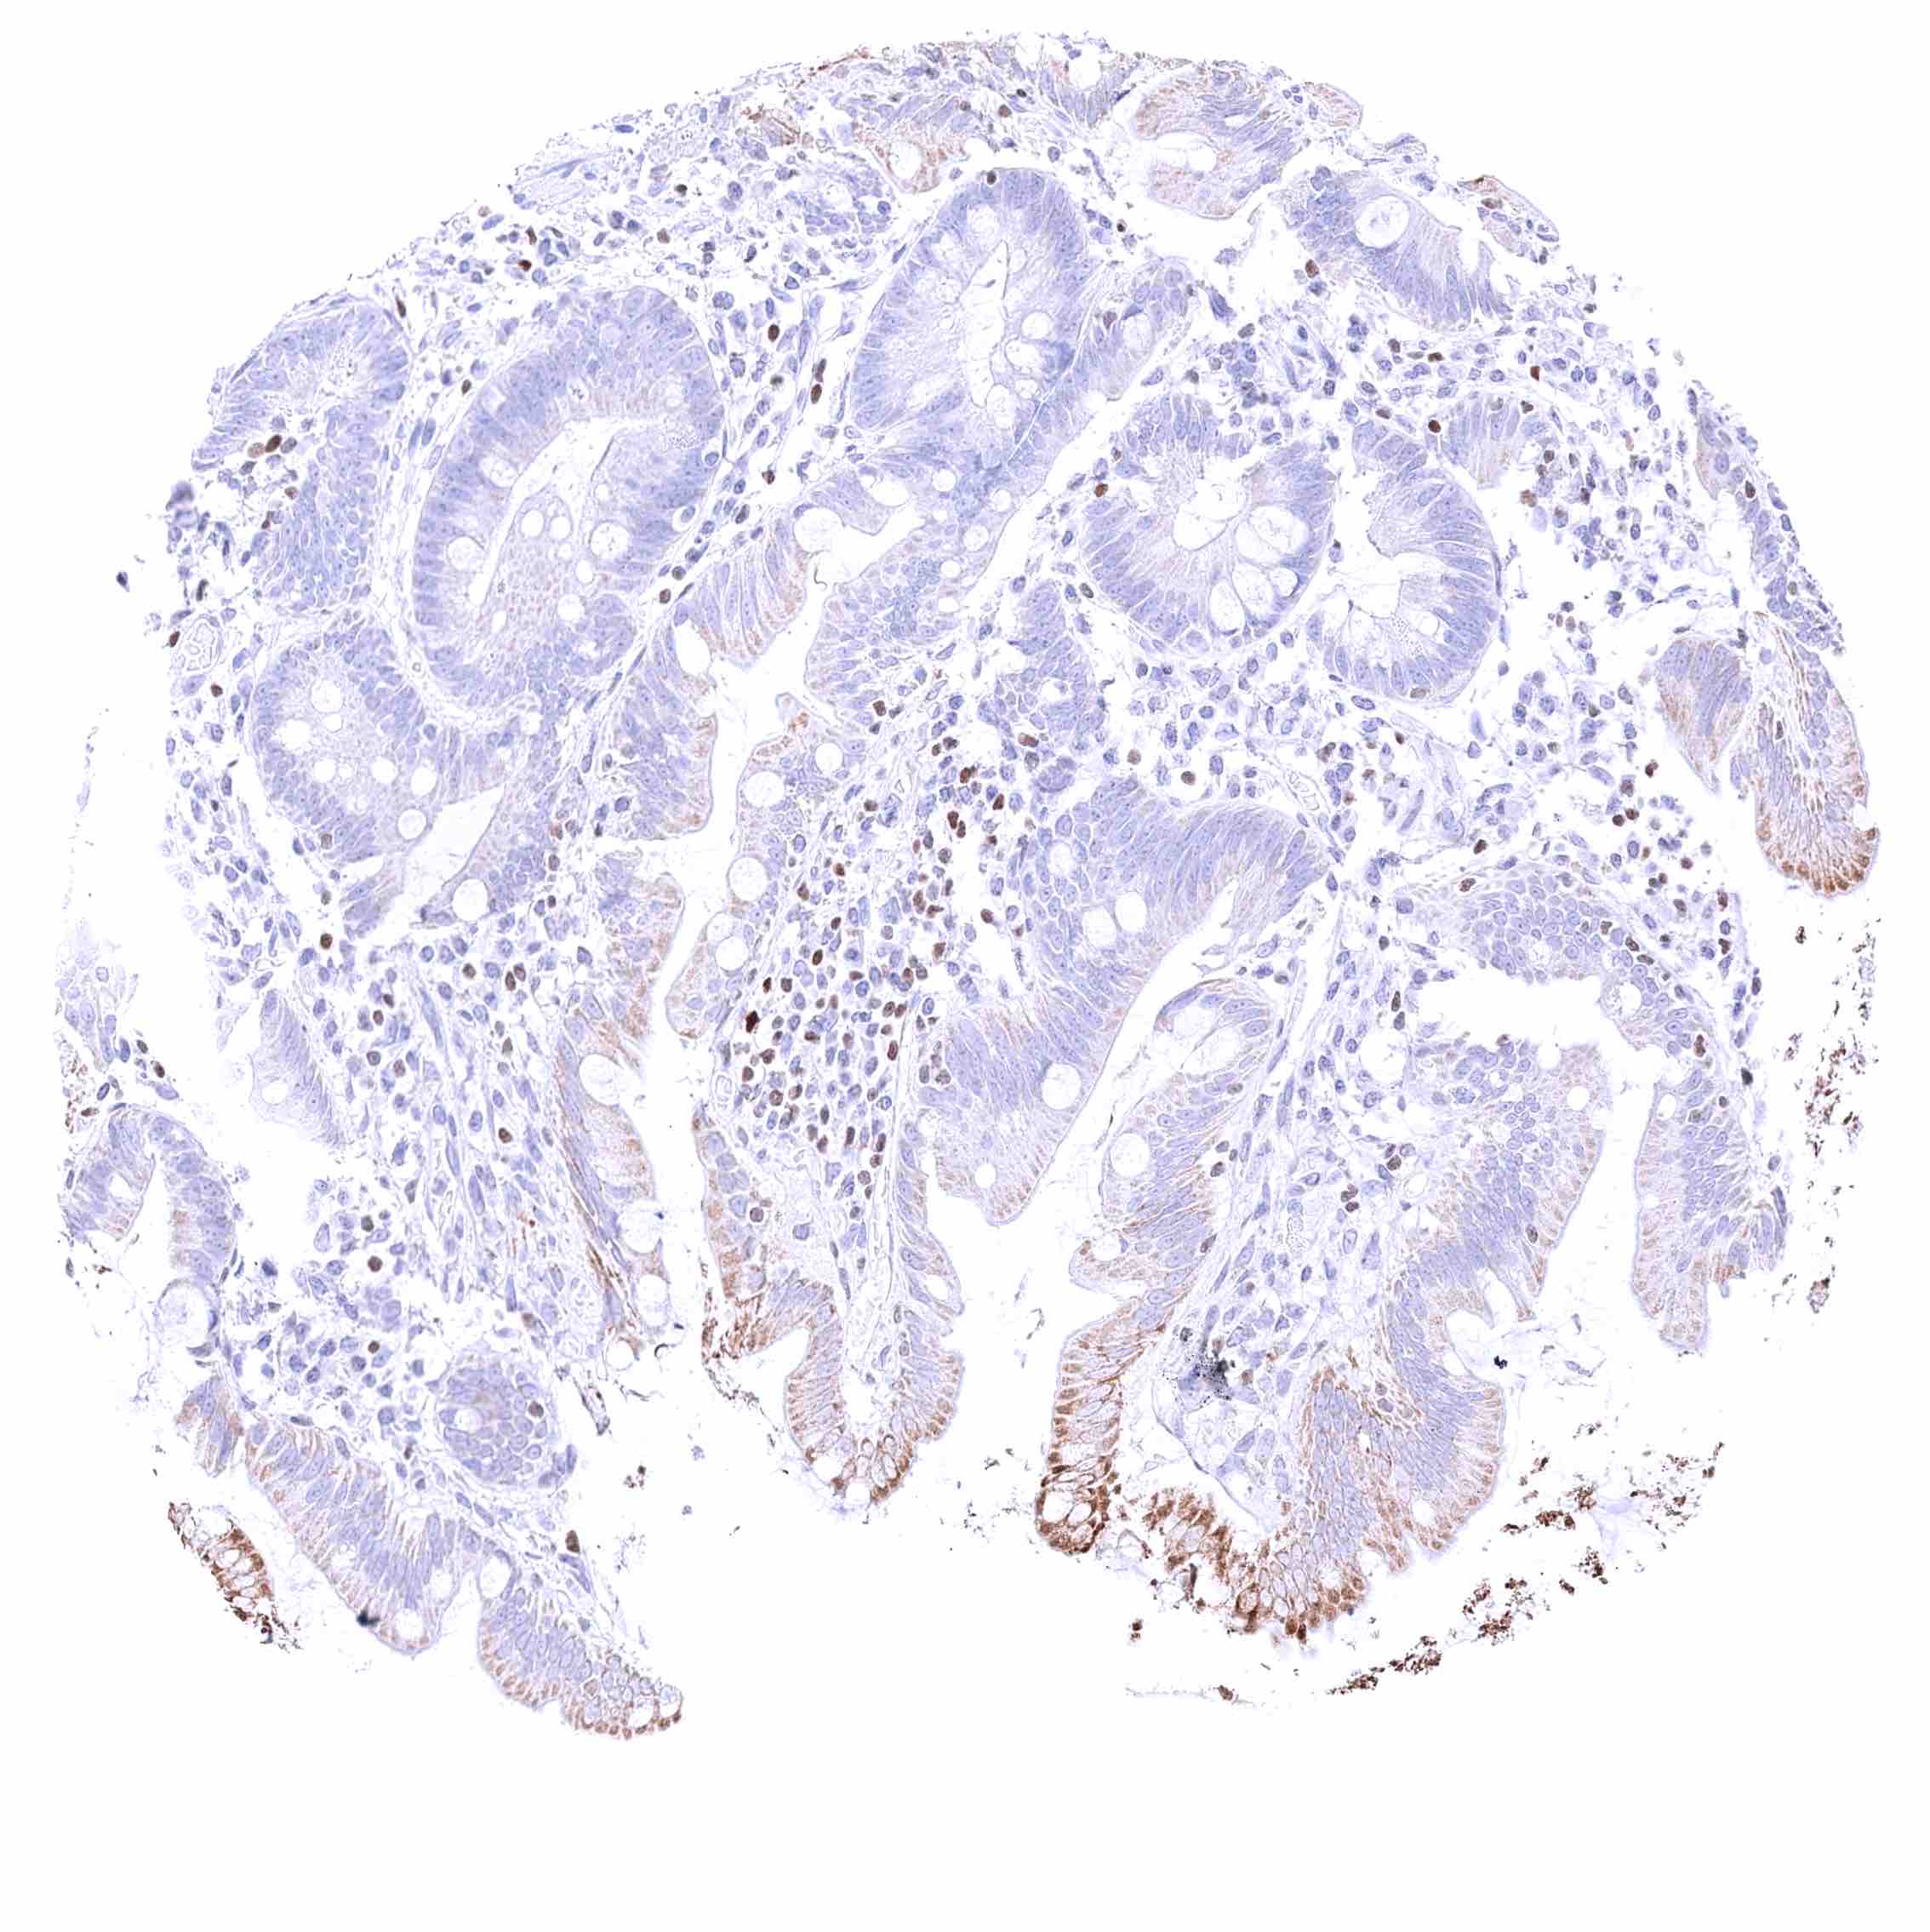

Colon descendens, mucosa – Nuclear GATA3 positivity of few lymphocytes. Faint cytoplasmic GATA3 positivity of some epithelial cells.

Rectum, mucosa – Nuclear GATA3 positivity of many lymphocytes.

Rectum, mucosa – Nuclear GATA3 positivity of some lymphocytes. Granular cytoplasmic GATA3 staining of epithelial cells.